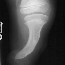

PHYSICAL EXAM: Examination of the right lower extremity demonstrates shortening of the right thigh with a 10 degree flexion contracture present in the knee. The knee is noted to be in valgus. There is moderate anteromedial bowing present in the leg with a dimple present over the anterior aspect of the tibia at the apex of the bow. The foot is held in a position of severe equinovalgus with absence of the lateral two rays noted. There is syndactyly present among the remaining digits. Circulation is normal and skin condition is good. Overall, the right lower extremity is noted to be 5 cm. shortened when compared to the contralateral normal extremity. Attempts at ambulation were limited by the severe deformity present in the right lower extremity.

RADIOGRAPHS: Absent right fibula and lateral two rays of right foot with moderate anteromedial bowing of tibia. The right femur was also noted to be shortened.